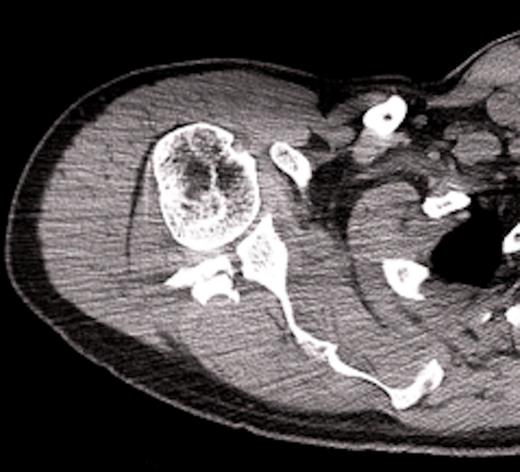

On examination there was restriction of the range of movement of the right shoulder with tenderness and swelling over the scapular. The skin was intact. There was no neurovascular deficit and the patient was otherwise physically well. X-rays revealed a fracture of the body of the scapula with posterior displacement of the inferior fragment. The shoulder joint was not dislocated and there were no associated fractures of the proximal humerus. The patient was admitted for analgesia and computed tomography was performed to assess the fracture. The scan showed involvement of the glenoid, with the fracture extending through the posterior lip. This was deemed inappropriate for surgical fixation. The patient was managed in a broad arm sling and discharged with simple range of movement exercises.

Computed tomographic scan, showing fracture extension into glenoid